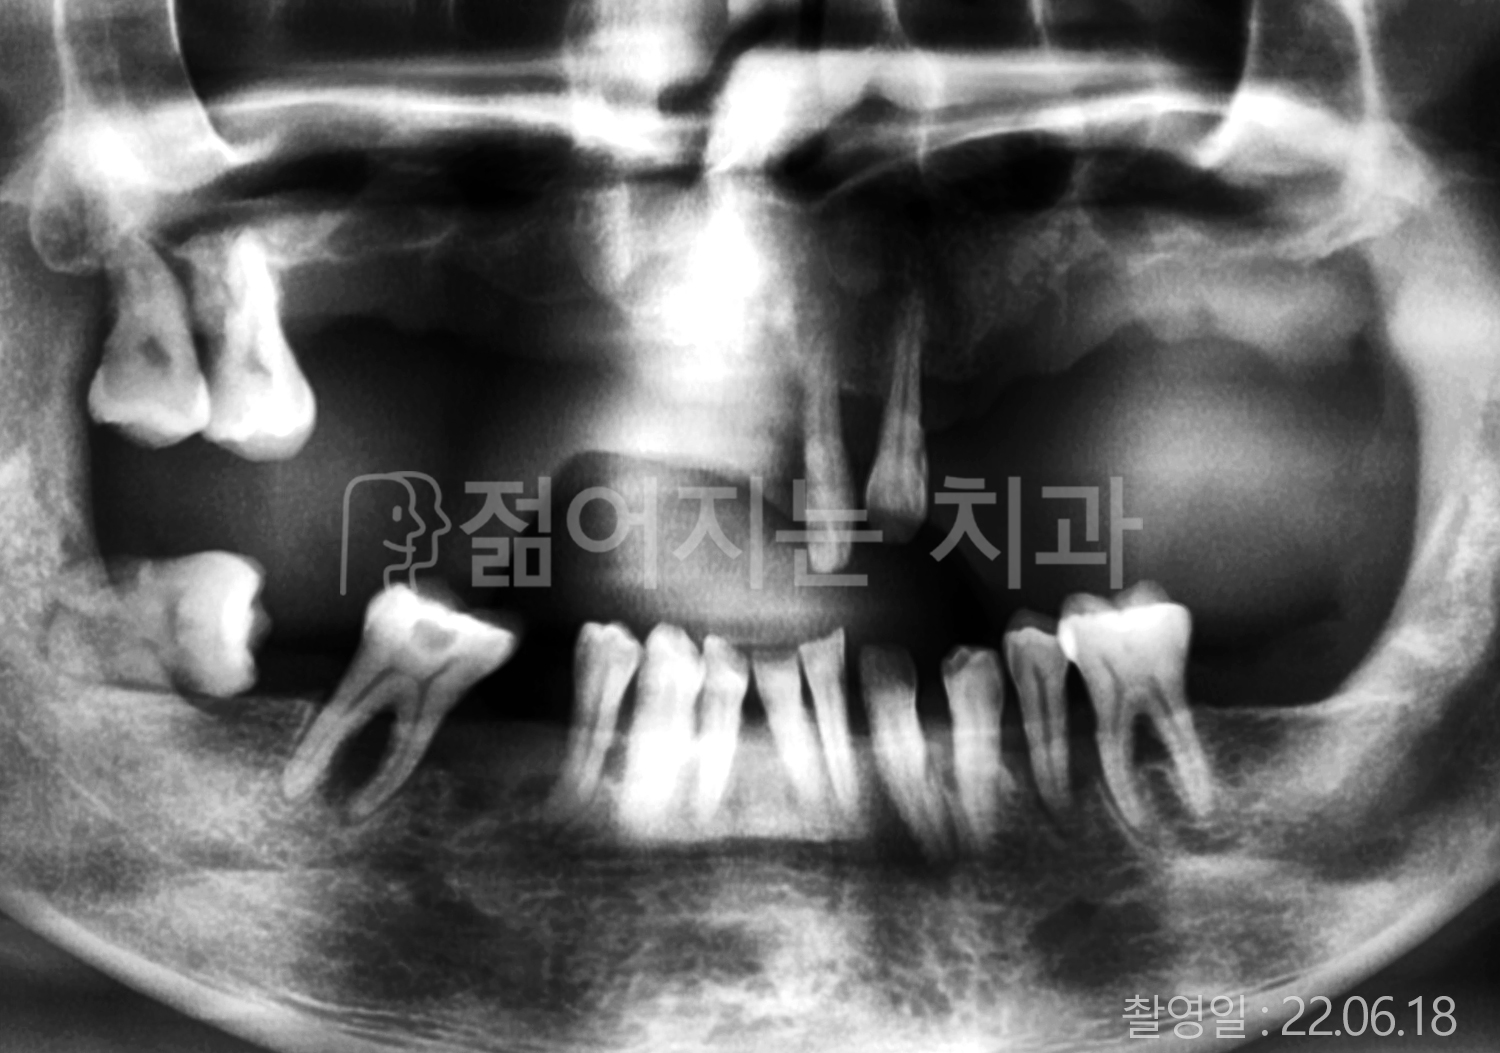

• 50대 전체치아 10개 이상 임플란트

• 50대 고혈압, 고지혈증 전체치아 10개 이상 임플란트